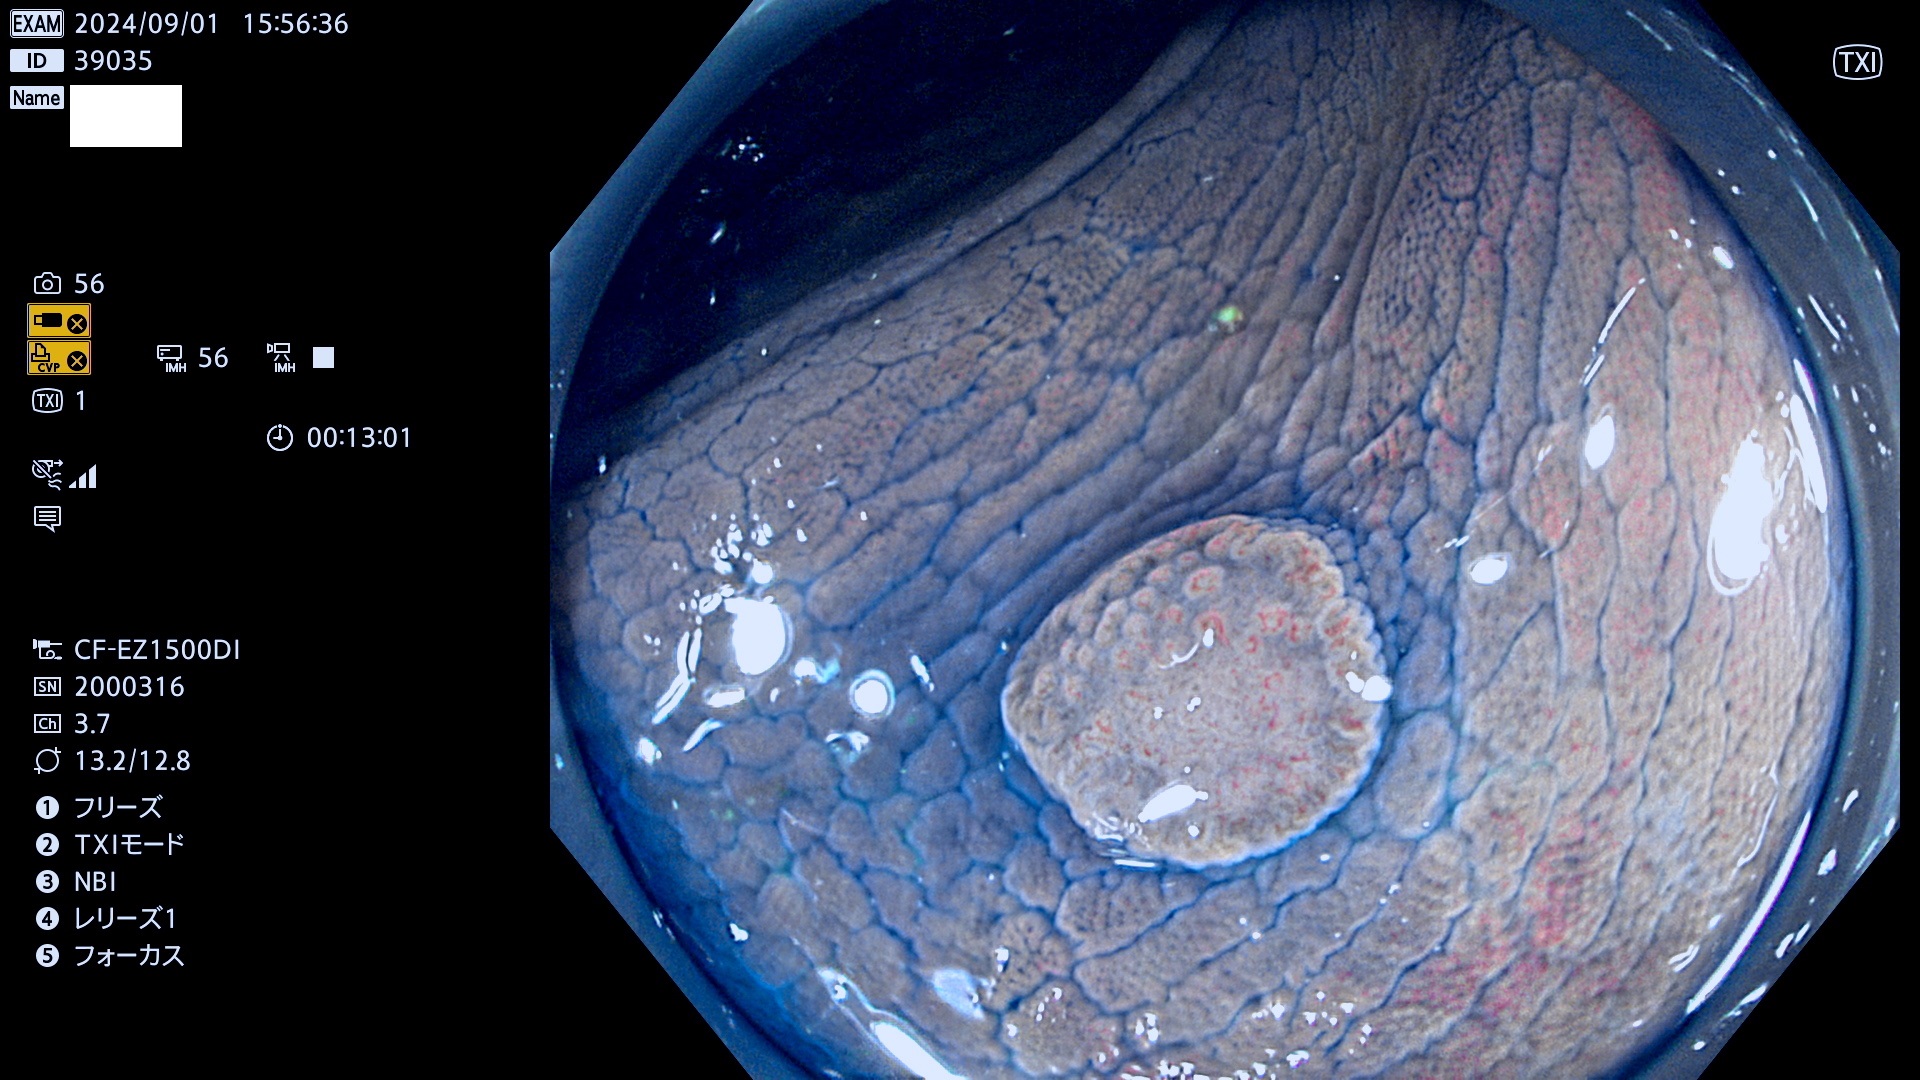

完全に平坦な物をUb、陥凹している物をUcと呼びます。最も発見が難しく危険な病変です。

抽出の対象期間 2024年8月29日〜9月1の4日間(40件の検査)5件 (5/40=13%)